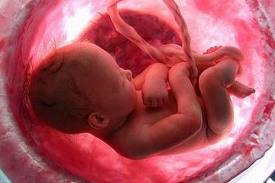

Ora il bambino ha assunto la posizione cefalica, ossia la posizione a testa in giù, ed è possibile avvertire dei fastidi sul collo dell’utero e sulle ossa pubiche. In realtà, sotto l’effetto della relaxina, i legamenti delle articolazioni fisse si ammorbidiscono, per facilitare il passaggio del bambino durante la nascita.

Il bambino è arrivato a pesare circa 2750 grammi ed è lungo circa 48 centimetri. Il suo corpicino comincia a perdere la peluria e la vernice caseosa che l’ha ricoperto finora per proteggerlo dall’azione irritante del liquido amniotico. Queste e altre sostanze sono ingerite dal piccolo con il liquido e vanno a formare il meconio.